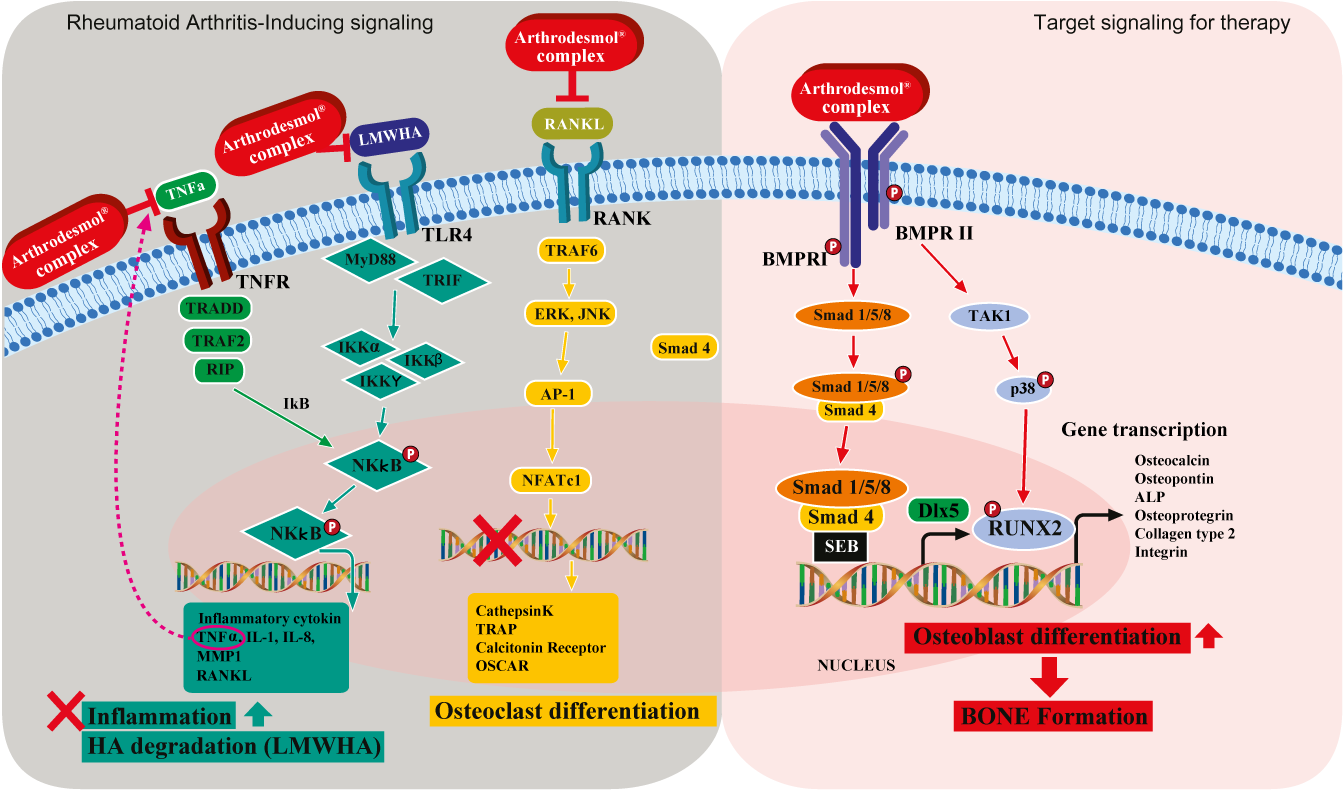

Signaling pathway of ARTHRODESMOL

TNFR signaling pathway activated by TNFα : blocked by CG-Inflendin / CG-Flatin (Anti-inflammation)

Often, the arthritis including the rheumatoid starts with the inflammation in synovial membrane of the joint.

The expression of inflammatory cytokine such as TNFα, IL-1, IL-8, MMP, and RANKL is strong in inflammatory tissue.

One TNFα binds to the TNF receptor (TNFR), it leads to the expression of TRADD, TRAF2, RIP.

TRADD, TRAF2, RIP are the signaling molecules expressed by the binding of TNFα to its binding site, and expression of these molecules lead to the phosphorylation of NKkB.

Then Phosphorylated NKkB promotes the synthesis of inflammatory cytokine such as TNFα, IL-1, IL-8, MMP, and RANKL.

So this pathway is cycling.

More and more inflammatory cytokines in body lead to the stimulation of inflammatory cytokine synthesis, and the vicious cycle of inflammation starts.

CG-Inflendin and CG-Flatin blocks the binding of TNFα to its binding site, so it can also stop the cycle of inflammation.

TLR4 signaling pathway activated by LMWHA (Low Molecular Weight Hyaluronic Acid): blocked by CG-Seperin (Anti-inflammation)

CG-Seperin is a MMP blocker and also the inhibitor of LMWHA binding to TLR4 site.

Low Molecular weight HA is degraded hyaluronic acid which also causes inflammation by promoting synthesis of inflammatory cytokines.

Once LMWHA binds to TLR4, MyD88 and TRIF (signaling molecules) expressed, and they lead to the expression of IKK molecules,

then expression of IKK molecules lead to the phosphorylation of NKkB.

So as a result, synthesis of inflammatory cytokine such as TNFα, IL-1, IL-8, MMP, and RANKL happens.

CG-Seperin down regulates the breakdown of HA, so it keeps the HA to have higher molecular weight.

RANK signaling pathway activated by RANKL : blocked by CG-Bonade / CG-Dentide (Anti-osteoclastogenesis)

RANKL is a cytokine which promotes the osteoclastogenesis.

Osteoclast is the changed form of bone tissue, and it leads to the damage in bone tissue.

Binding of RANKL to its binding site leads to TRF6 expression → ERK, JNK → AP-1 →NFATc1 expression.

Then this pathway ends up with the expression of the gene which promotes the osteoclastogenesis.

CG-Bonade and CG-Dentide blocks the RANKL binds to its binding site, so it inhibits the osteoclastogenesis.

You can see its efficacy in osteoclastogenesis inhibition in the in-vitro study data C. in the leaflet too.

BMPR signaling pathway activated by CG-Bonade / CG-Dentide (Bone formation)

Not only inhibiting the RANKL, CG-Bonade and CG-Dentide also binds to the BMP binding site and promotes the bone formation.

CG-Bonade and CG-Dentide can binds to the BMPR and activate BMP pathway.

This signaling pathway ends up to the expression of gene transcription for bone formation including the osteoblast (bone cell) genesis.

By this bone formation, the cartilage (bone tissue) can be regenerated through the time.

TRADD, MyD88, TRAF6, and etc are the signaling molecules in cytosol, and the expression of each molecule leads to the expression of another signaling molecule in the path way.